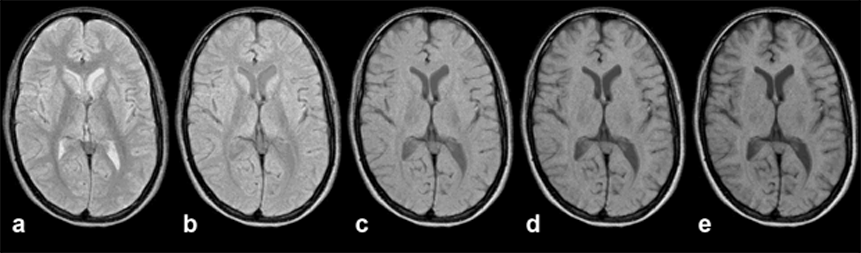

Figures 10-12 and 10-13 depict the typical signal intensity behavior of a GRE se­quen­ce, in this case a spoiled FLASH sequence. Commonly, the signal in­­ten­­si­­ties reach a maximum between 30° and 60°.

As we have seen with the signal in­ten­si­ty and contrast behavior of SE sequences, best contrast is not necessarily ob­tai­ned at the point of highest signal intensity. This is also the case in GRE se­que­nces, as the con­trast be­ha­vior of the brain images of Figure 10-13 shows. At the greatest signal in­ten­si­ty, there is poor or no contrast.

It turns out that images acquired using the Ernst angle tend to have rather poor con­trast. Higher flip angles have to be used to improve the contrast. The effect of this is a reduction of the signal left along the z-axis after the RF pulse. Thus, the sig­nal level depends on the rate at which the si­gnal recovered during TR; it is strong­ly T1-dependent. The image series in Figures 10-12 and 10-13 give an over­view of how contrast changes with in­­crea­s­ing flip angle.

Figura 10-13:

Gradient echo pulse sequence (spoiled GRE) through the brain of a patient with a vascular mal­for­ma­tion in the right occipital hemisphere.

The upper image series was ta­ken with an echo time TE = 20 ms, the lower series with an echo time TE = 120 ms (B₀ = 1.5 T). The lesion is nearly invisible in the image series with short TE, but well de­li­ne­at­ed in the series with long TE.

As we have seen in the SE se­quen­ces, one can hide and miss pathological chan­ges by choosing the wrong pulse se­quen­ce. This also holds for rapid se­quen­ces. If we se­lect a T1-weighted se­que­nce, we cannot distinguish a lesion which possesses a si­mi­lar T1 to its neighboring tissues. If we apply a T2*-weighted sequence, we cannot de­li­ne­ate a lesion with a T2 close to the T2 of its surroundings. The signal intensity of the vascular malformation in Figure 10-13 is a good example of this problem.